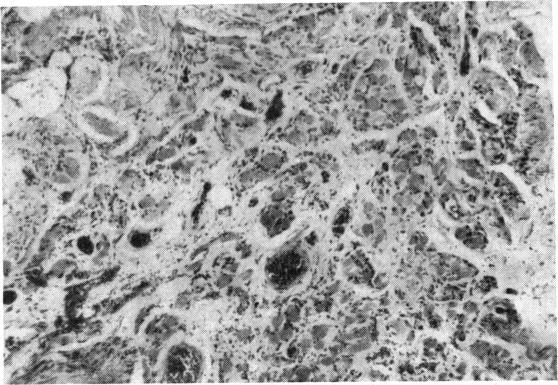

PROGRESSIVE MUSCULAR DYSTROPHY INVOLVING THE EXTRA-OCULAR MUSCLES WITH NOTES CONCERNING OPERATIVE TREATMENT OF THE ASSOCIATED DIVERGENT SQUINT.

Br J Ophthalmol. 1965 Feb;49(2):102-5. doi: 10.1136/bjo.49.2.102.